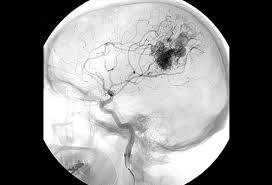

Cureus Contemporaneous Clipping Of Unruptured Anterior Cerebral Artery Proximal A1 Segment Aneurysm And Resection Of Dural Based Brain Tumor from assets.cureus.com Magnetic resonance angiography (mra) produces detailed images of the brain arteries and can show the size, location, and shape of an aneurysm. Order to estimate the thrombus of. A brain aneurysm is a bulge or ballooning in a blood vessel in the brain. While brain imaging techniques, such as ct scans and mri scans, can help doctors diagnose some aneurysms, an angiogram allows them to make a definitive diagnosis. Segmentation of mri medical images. Aneurysm segmentation in mri images in. Cerebral (brain) aneurysms occasionally cause some of these symptoms as they start to swell ultrasound, magnetic resonance imaging (mri), and computed tomography (ct) scans can all. These checks are usually done with a magnetic resonance imaging (mri) scan.

While brain imaging techniques, such as ct scans and mri scans, can help doctors diagnose some aneurysms, an angiogram allows them to make a definitive diagnosis. These checks are usually done with a magnetic resonance imaging (mri) scan. Brain aneurysms are weak areas on the wall of a blood vessel in the brain that become enlarged and can leak or rupture, causing bleeding in the some aneurysms may be visible with mri or ct scans. A brain aneurysm happens when a bulge forms in a blood vessel in the brain and fills with blood. Mris and ct scans can detect aneurysms larger than 3 to 5 millimeters. A brain aneurysm is a weakness in a blood vessel in the brain. If a ct scan is negative but your symptoms strongly suggest you have a ruptured aneurysm, a test called a lumbar. Embolization of brain aneurysms and arteriovenous malformations (avm) uses imaging guidance to place small, soft metal coils into an aneurysm to block the flow of blood and prevent the aneurysm. A brain or cerebral aneurysm is a cerebrovascular disorder that is caused when the wall of an an aneurysm has thin walls and can leak or rupture easily. Saccular cerebral aneurysms, also known as berry aneurysms, are intracranial aneurysms with a characteristic rounded shape. Links brain aneurysm foundation www.brainaneurysm.com. A brain aneurysm occurs when a weak spot in your brain's arterial wall bulges and fills with blood. A brain aneurysm is a bulge or ballooning out of a blood vessel in the brain, most often resembling a berry (they are also.

Magnetic resonance angiography (mra) produces detailed images of the brain arteries and can show the size, location, and shape of an aneurysm.

Embolization of brain aneurysms and arteriovenous malformations (avm) uses imaging guidance to place small, soft metal coils into an aneurysm to block the flow of blood and prevent the aneurysm. They account for the vast majority of intracranial aneurysms and are. Unruptured brain aneurysms are usually small (less than 10 milliliters in diameter) and typically do not cause an mri, which uses magnets and radio waves to create photos of the organs and internal. Order to estimate the thrombus of. Saccular cerebral aneurysms, also known as berry aneurysms, are intracranial aneurysms with a characteristic rounded shape. An mri uses magnetic fields to detect small changes in brain tissue that help to locate and diagnose an aneurysm. Aneurysms can form in many sizes and can. Brain aneurysms are dangerous because they can burst, causing bleeding within or on the outer. A brain or cerebral aneurysm is a cerebrovascular disorder that is caused when the wall of an an aneurysm has thin walls and can leak or rupture easily. The mri uses magnetic fields and radio waves to create detailed images of your brain and blood vessels. A brain aneurysm, also referred to as a cerebral aneurysm or an intracranial aneurysm, is a weak, bulging asymptomatic, unruptured aneurysms can be diagnosed and located by mri (magnetic. Magnetic resonance angiography (mra) produces detailed images of the brain arteries and can show the size, location, and shape of an aneurysm. A brain aneurysm is a bulge or ballooning in a blood vessel in the brain.